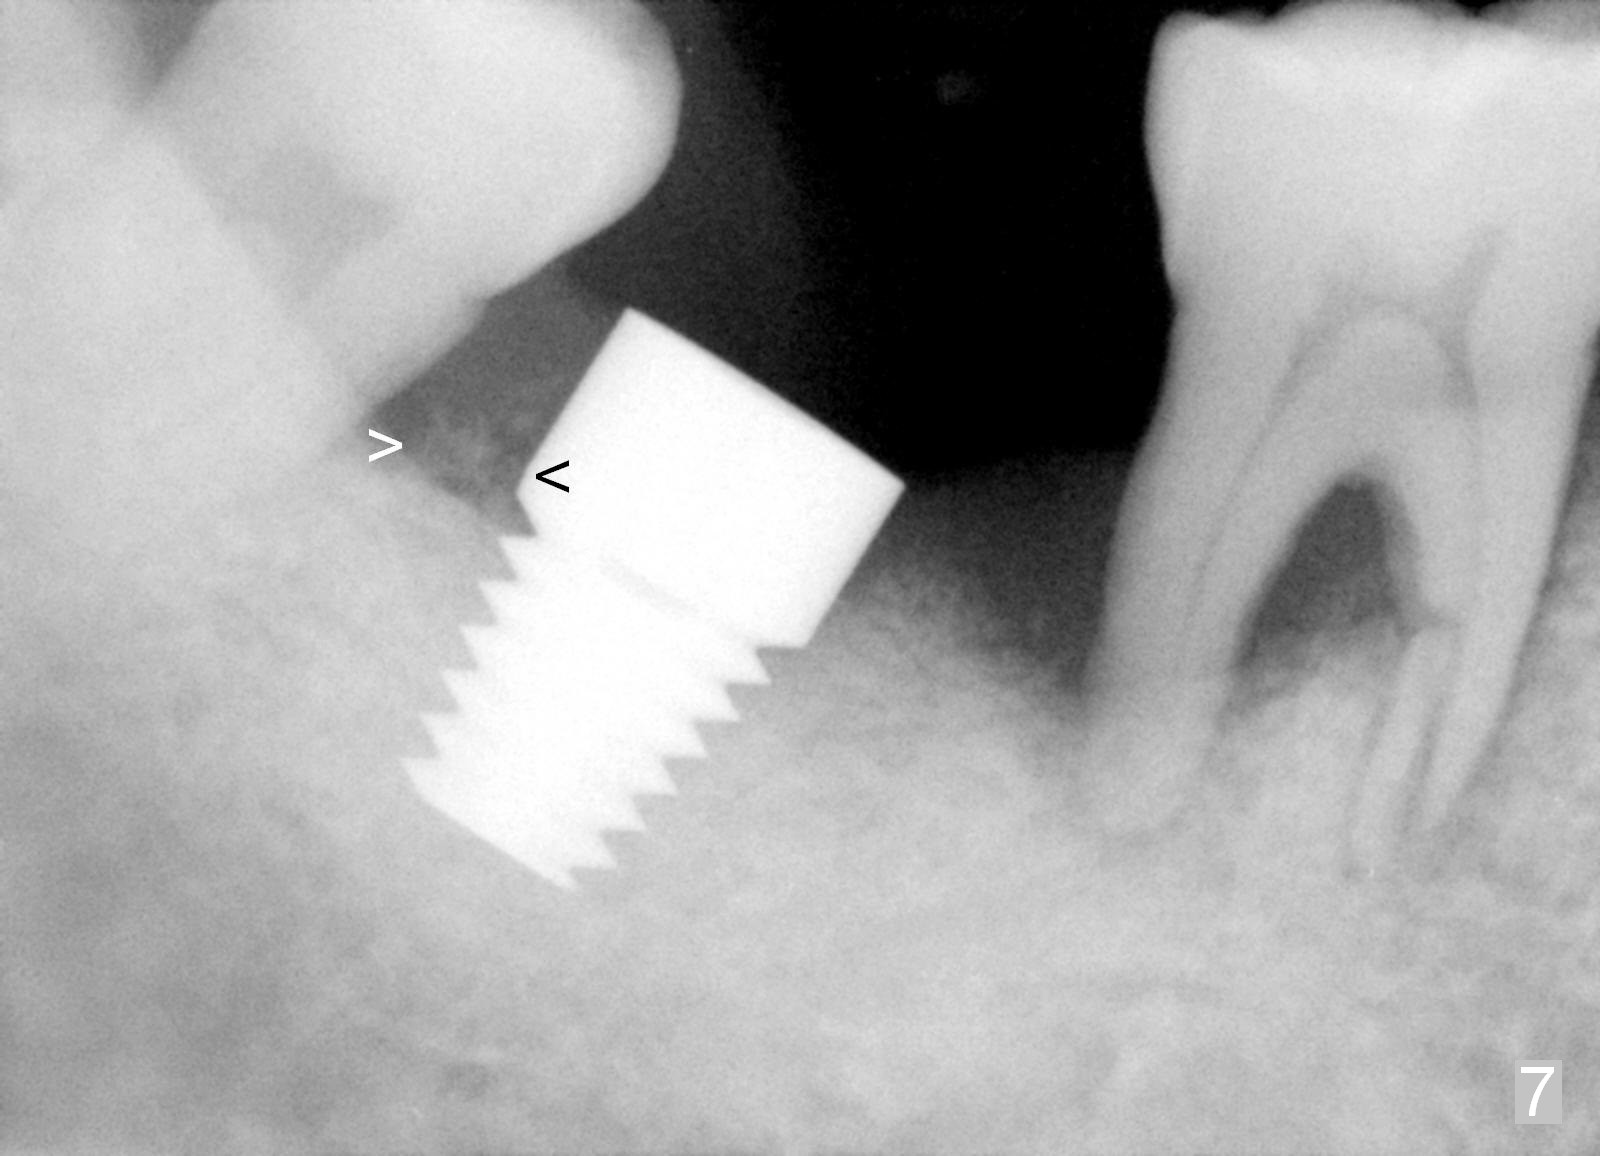

Luckily the patient returns for #31 implantation 4 months post socket preservation. Bone forms in the alveolus and above (Fig.1 black and white arrowheads, respectively). A 6 mm tissue punch is used to open the wound (Fig.2). Osteotomy forms using bone expanders, reamers and taps (Fig.3: 6x14 mm tap). Without infection, local anesthesia is more easily achieved than immediate implant when infection exists. The depth is controlled more readily with delayed implantation. Following adjustment of trajectory, a 7x11 mm implant is placed with insertion torque 60 Ncm (Fig.4 I). Fig.5 shows that the implant obliterates the wound; an abutment (A) is placed to retain perio dressing. With formation of new bone from socket preservation, insertion torque seems to be more easily obtained with the short implant. There is no space to re-use the harvested bone (Fig.6). The implant remains stable postop. Apparent new bone is forming toward the distal coronal threads 5 months postop (Fig.7). The bone around the implant remains stable 17 months post cementation (Fig.8), although there is an episode infection at the neighboring tooth (#30). The patient is more eager to have implants for the maxilla, since the flipper has lost. After implant placement at #7, the pain at #30 becomes more severe.